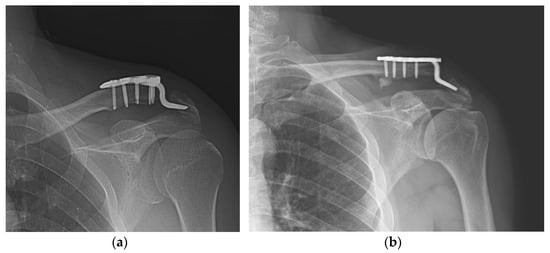

Figure 3. Acromial fracture. (a,b) Acromial fracture may be developed by frictional movement between the hook and the acromion; (c,d) fracture healing is shown without any additional procedure.

Varying degrees of subacromial erosion occurred in all patients, and acromial fracture occurred in one case in the DCF group and seven cases in the ACD group (Figure 2 and Figure 3). Five (6.7%) cases showed incomplete union and one (1.3%) case showed peri-implant stress fracture in the DCF group (Figure 4 and Figure 5). Four of the five cases of incomplete union showed fracture union without additional surgery during the follow-up period, and one case did not heal at the final follow-up, although the patient did not show any discomfort with non-union (Figure 6). The peri-implant fracture healed with conservative management before plate removal. LOR was observed in nine patients with ACD. Before removing the hook plate, LOR occurred in six patients with ACD. Among these six patients, five showed acromial fracture and one showed serious subacromial erosion (Figure 7). After removing the hook plate, LOR occurred in three patients during the follow-up period. However, none of these patients with LOR among patients with ACD showed tenderness on the acromioclavicular joint or pain during the follow-up period. Regarding acromial fracture, one (1.3%, 1 of 36) case was observed in the DCF group and seven (8.3%, 7 of 33) cases were noted in the ACD group (Figure 4). There was no difference in the incidence of acromial fracture between patients with DCF and ACD (p = 0.066). All eight patients had fracture union without additional surgical treatment during the follow-up period.

An acromial fracture is probably a result of subacromial erosion. Several studies have reported the occurrence of acromion fractures at a weakened location [42,43,44]. Eight patients sustained acromion fractures in our study. In terms of the risk factors for PSS, acromial fracture cases were also not related to the incidence of PSS (Table 3). Therefore, incomplete fracture union and acromial fracture do not appear to affect the occurrence of PSS.